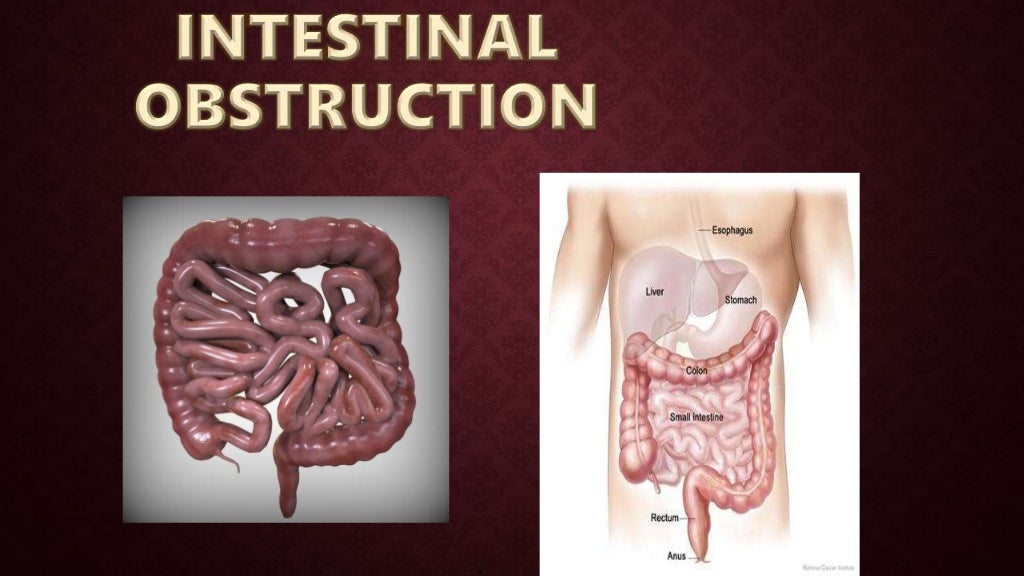

Intestinal Obstruction

Intestinal Obstruction

Intestinal Obstruction